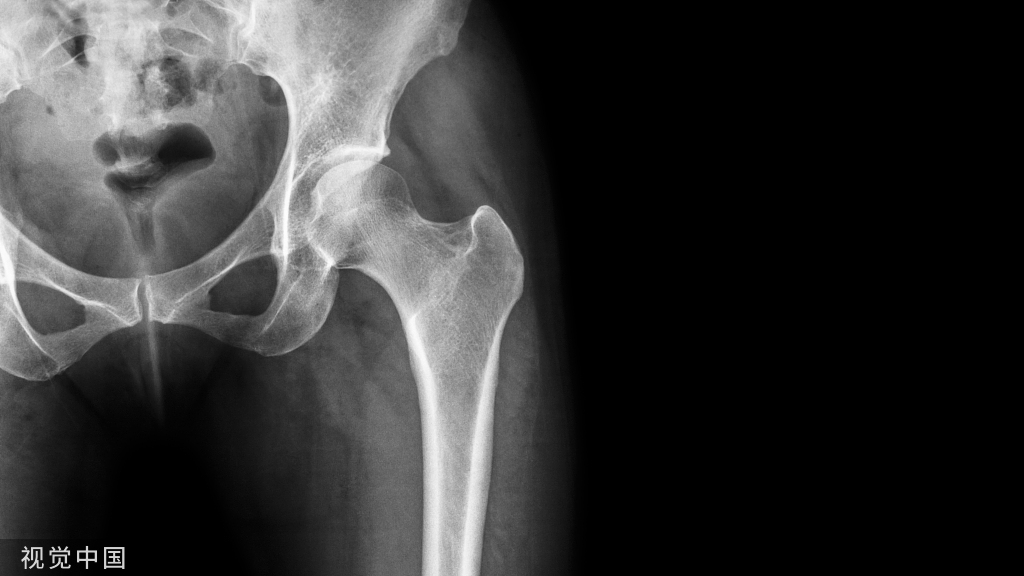

经皮空心钉固定适合于骨折块较大,移位较少,骨质好的患者。具有微创损伤小、不干扰局部的血运、固定牢靠、恢复快等优点。

操作要点:操作要在透视监视下进行,且导针一定要从尖端打入,且在第四、五跖骨间连接以远穿出对侧骨皮质,这样生物力学强度最佳。